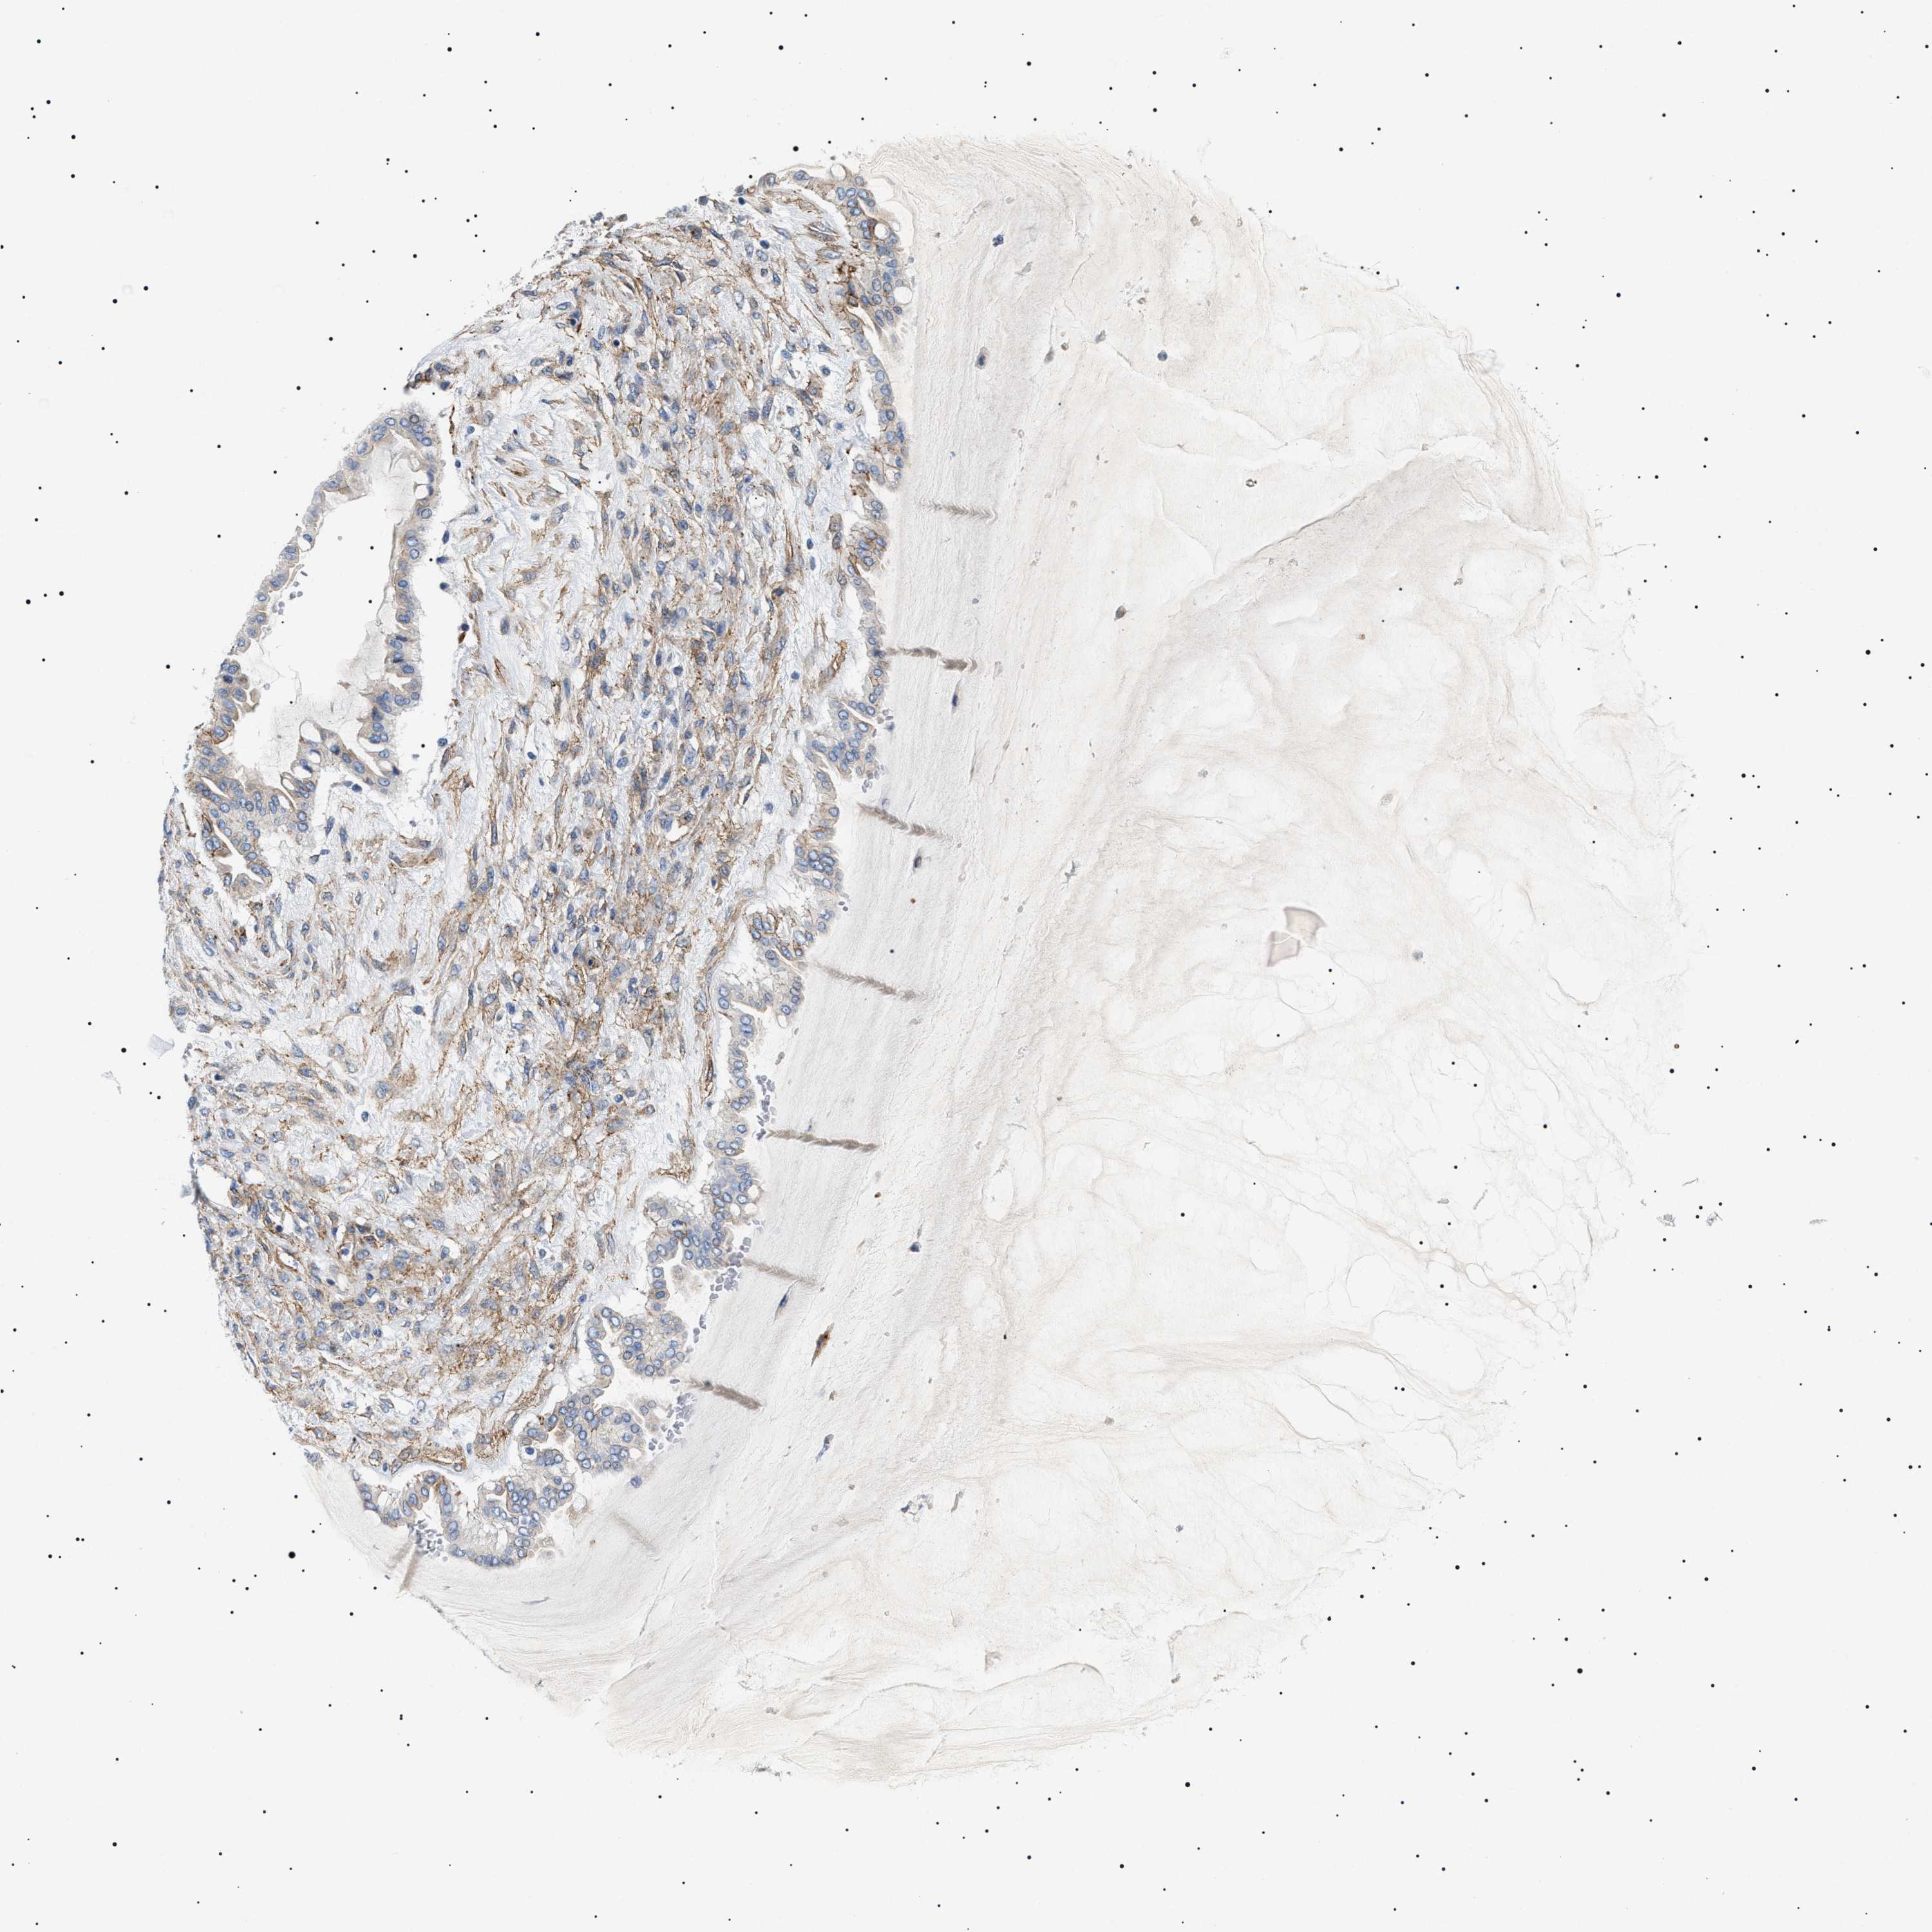

OVARIAN CANCER - Protein expressioni

A mouse-over function shows sample information and annotation data. Click on an image to view it in a full screen mode. Samples can be filtered based on level of antibody staining by selecting one or several of the following categories: high, medium, low and not detected. The assay and annotation is described here.

Note that samples used for immunohistochemistry by the Human Protein Atlas do not correspond to samples in the TCGA dataset.

Antibody stainingi

Antibody staining in the annotated cell types in the current human tissue is reported as not detected, low, medium, or high, based on conventional immunohistochemistry profiling in selected tissues. This score is based on the combination of the staining intensity and fraction of stained cells.

Each image is clickable and will lead to virtual microscopy that enables deeper exploration of all samples and also displays staining intensity scores, fraction scores and subcellular localization as well as patient and tissue information for each sample.

Antibody HPA016579

Antibody HPA059374

Cystadenocarcinoma, serous, NOS

Carcinoma, endometroid

Cystadenocarcinoma, mucinous, NOS

Carcinoma, NOS